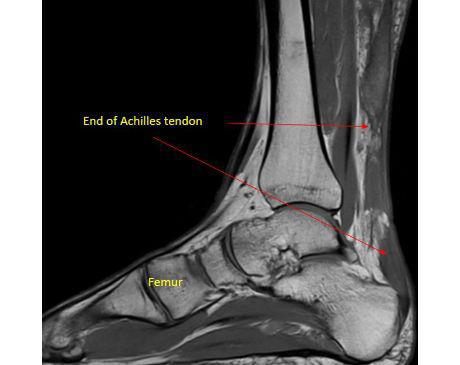

I was hit by car, had a compound fracture with a bone sticking out of my left foot. Broken tibia and fibia?. Screwed plate and bones back together. I am healing fine, next visit 3/26 to remove stiches. I seem to have total function of foot. Still have 2 more weeks of not using leg, but very hopeful.